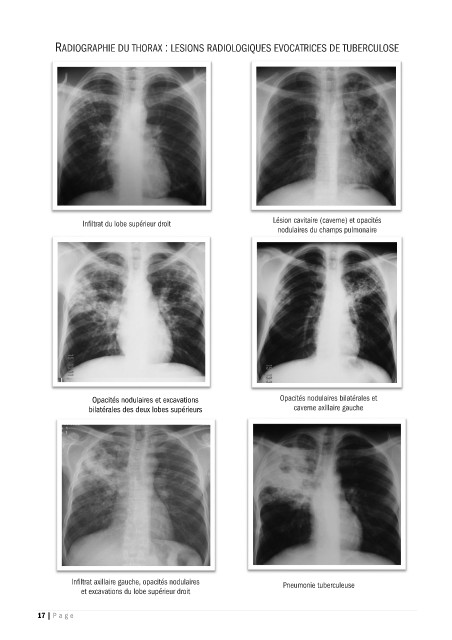

RADIOGRAPHIE DU THORAX : LESIONS RADIOLOGIQUES EVOCATRICES DE TUBERCULOSE

Infiltrat du lobe supérieur droit Lésion cavitaire (caverne) et opacités

nodulaires du champs pulmonaire

Opacités nodulaires et excavations Opacités nodulaires bilatérales et

bilatérales des deux lobes supérieurs caverne axillaire gauche

Infiltrat axillaire gauche, opacités nodulaires Pneumonie tuberculeuse

et excavations du lobe supérieur droit